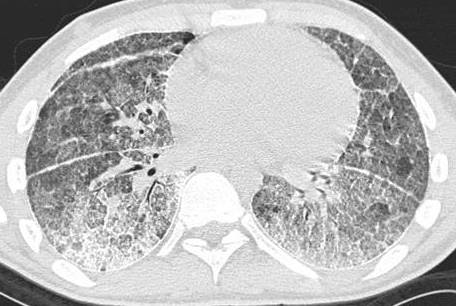

Figure 1. HRCT thorax from a patient with pulmonary alveolar microlithiasis (PAM).

Pulmonary function tests showed a mild restrictive pattern. HRCT imaging of the lungs showed bilateral calcifications with increased attenuation involving alveoli, intra- and interlobular septa, fissures and pleura.